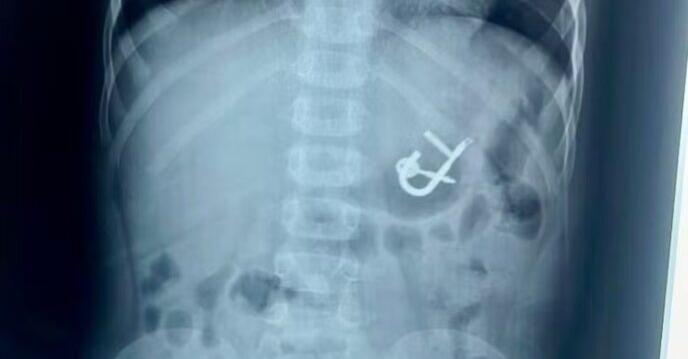

Uma criança de quatro anos engoliu um cadeado com as chaves em Cedro, no Sertão de Pernambuco. O menino deu entrada no último sábado (10) no Hospital Regional Inácio de Sá, em Salgueiro. O objeto foi retirado com sucesso, no mesmo dia, por meio de endoscopia digestiva, e o paciente já teve alta médica.

“Quando eu cheguei no raio x, já dava para ver que o cadeado estava no estômago. A nossa maior preocupação era o tempo de passar e esse cadeado progredir para o intestino, porque provavelmente ocasionaria uma obstrução intestinal, e realmente teria que ser cirúrgico. Então, rapidamente fomos para o bloco cirúrgico para fazer a anestesia da criança. O cirurgião Nairton estava a postos, se durante a retirada houvesse lesão no esôfago e precisasse de cirurgia de urgência. Felizmente, deu tudo certo, nós realizamos a retirada em aproximadamente 20 minutos”, explicou.

O menino ingeriu o objeto por acidente. “Ele estava brincando com o cadeado na boca, as chaves estavam presas ao cadeado. Ele estava tentando retirar a chave com a boca, aparentemente, se desequilibrou, caiu para trás e acabou engolindo um cadeado de aproximadamente cinco centímetros, que estava fechado com a chave”, esclareceu.